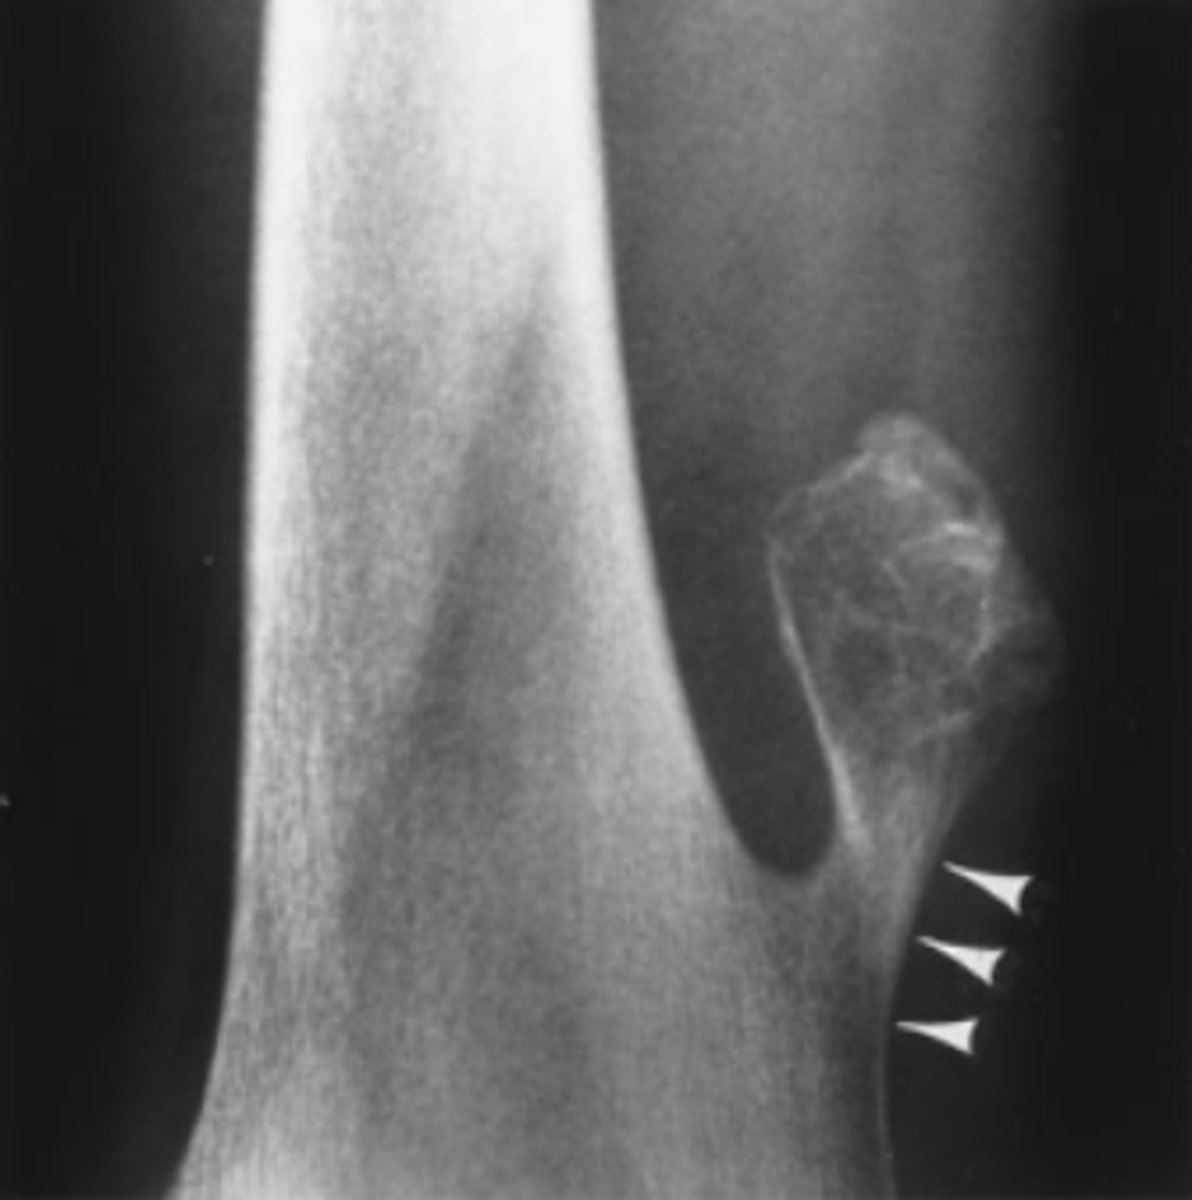

A 35-year-old man complains of a lump in the soft tissues of the right arm. He first noticed the lump 6 months ago after hurting his arm in a fall from a bicycle (AP view of the arm).

What should you do about the calcified lump in the

patient's arm in Case 6-8 (Figure 6-21)?

A. Needle biopsy

B. Open excisional biopsy

C. Reassure the patient

D. Bone scan

Answer

C.

Well defined ossified mass projecting into the musculature of the posterolateral arm. It has a thin but distinct cortex surrounding the trabeculae. It is myositis ossificans